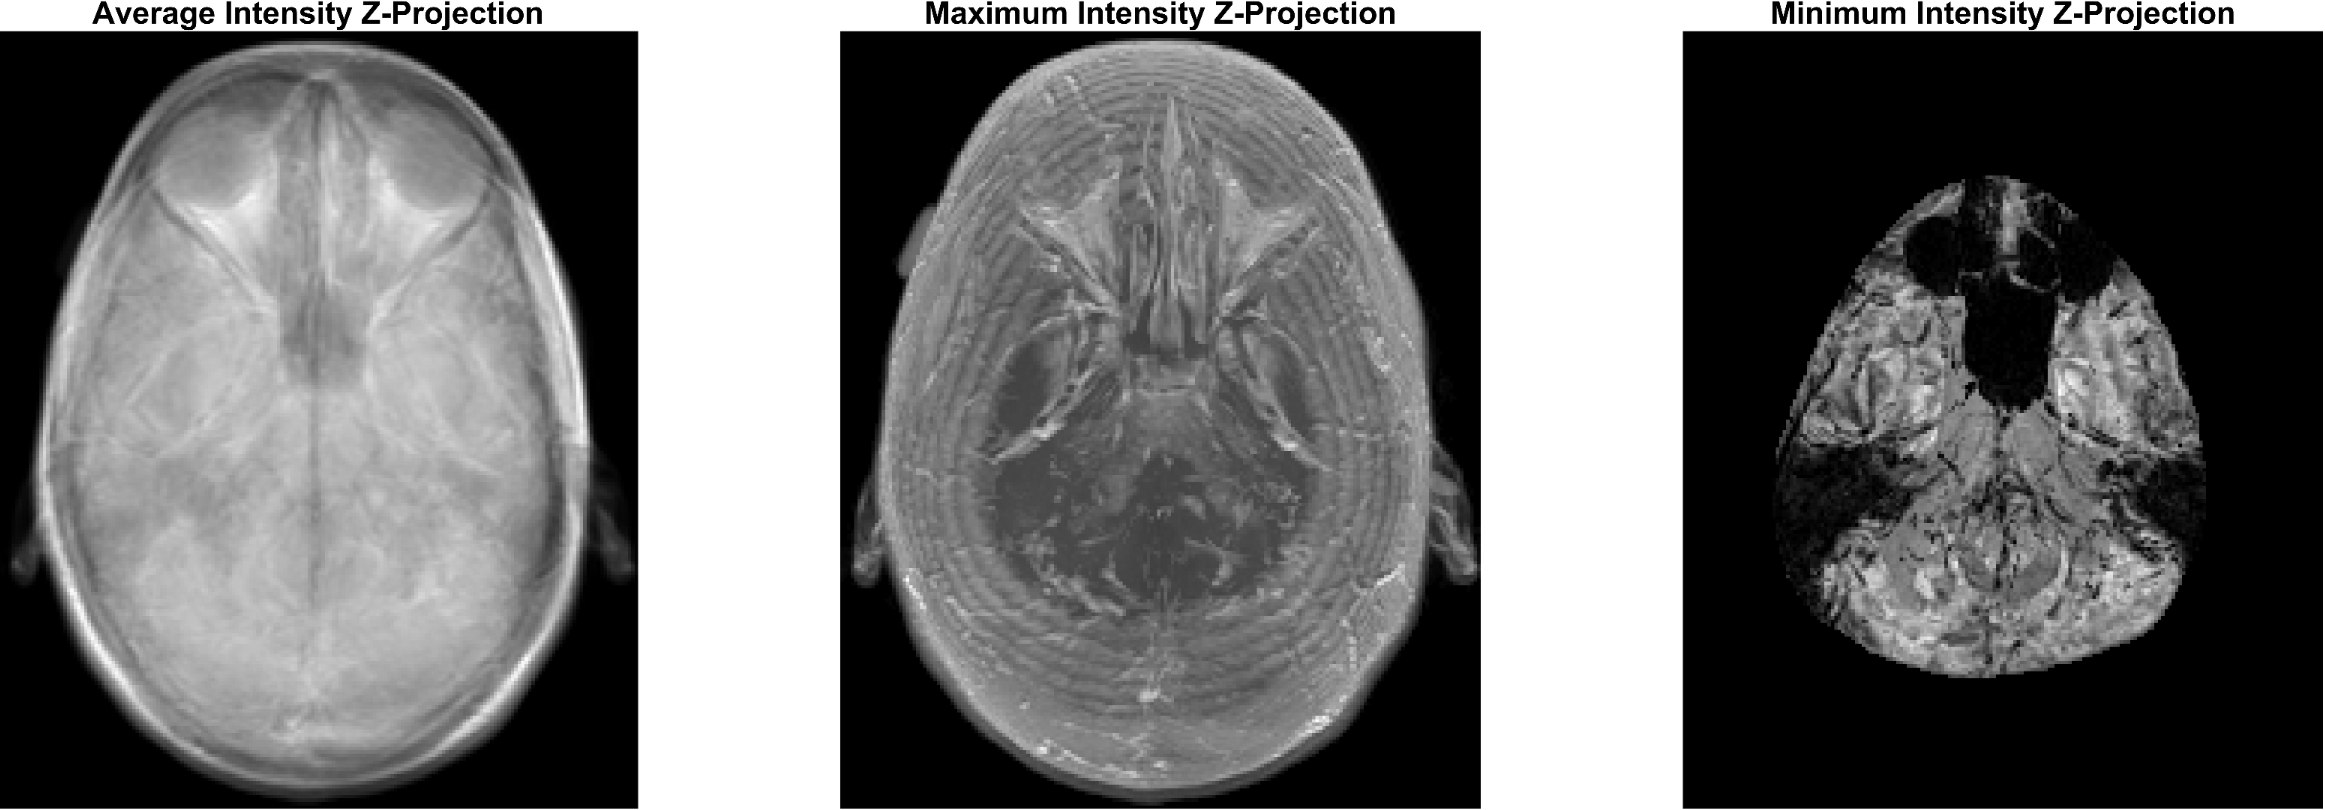

Medical 또는 microscope imaging 분야에서 (위의 MRI 이미지 같이) z축 방향으로

- 이미지의 너비, 높이를 각각 x, y 방향이라 가정한다면 z방향은 이미지의 깊이 -

2차원 이미지를 켜켜이 겹쳐놓은것을 z-stack image 이라고 합니다.

( 위의 MRI 이미지 또한 z-stack image 이라고 할 수 있습니다. )

이미지 프로세싱/분석의 목적에 따라 z-stack image의 구조적, 기능적 특징을 검출하는

다양한 테크닉이 활용됩니다. 간단한 예로써, MRI 영상의 전체 layer 이미지 픽셀값의 평균을

이용한 average intensity z-projection, 픽셀의 최대, 최소값을 이용한 maximum/minimum

intensity z-projection 을 다음과 같이 보여 줍니다.

Average intensity z-projection의 경우, 각 layer의 이미지들을 더한(= 선형 합) 다음

layer의 수만큼 나누어 픽셀값 평균을 구하였습니다.

figure;

subplot(1,3,1); imshow(img_mean_stack,[ ], 'InitialMagnification', 'fit');  title('\fontsize{20}Average Intensity Z-Projection');

subplot(1,3,2); imshow(img_maxP,[ ], 'InitialMagnification', 'fit'); title('\fontsize{20}Maximum Intensity Z-Projection');

subplot(1,3,3); imshow(img_minP,[ ], 'InitialMagnification', 'fit');  title('\fontsize{20}Minimum Intensity Z-Projection');